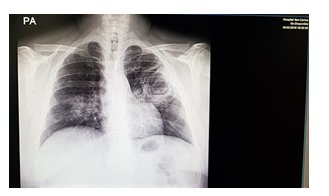

The chest X-ray that we observed in Figure 1 showed a right paracardiac consolidation and a left paracardiac image similar to a cavern or a consolidation in formation, without pleural effusion and with a normal cardiac silhouette.

Figure 1 Pulmonary tuberculosis cavitated.

On the other hand, the chest X-ray was decisive in the presumptive diagnosis of pulmonary tuberculosis, however; radiographically, the differentiation between active and inactive disease can only be made according to the evolution over time.4

Castiñeira mentions that the typical radiological aspect of an acute pulmonary tuberculosis is of air spaces characterized by a homogeneous opacity of ill-defined edges. It is often indistinguishable from typical bacterial pneumonia. Important keys for diagnosis are associated lymphadenopathy (the presence of parenchymal disease in the absence of adenopathy appears only in 1% of pediatric cases and in 38-81% of adult primary TB), the lack of systemic toxicity (tuberculous pneumonia can be seen as a casual finding in an asymptomatic patient) and failure in the response to conventional antibacterial therapy. Cavitation is a rare manifestation of primary tuberculosis in infants and children living in communities long exposed to the tubercle bacillus. It has been found in 7-29% of adults and occurs in 40-87% of patients with post-primary tuberculosis.4